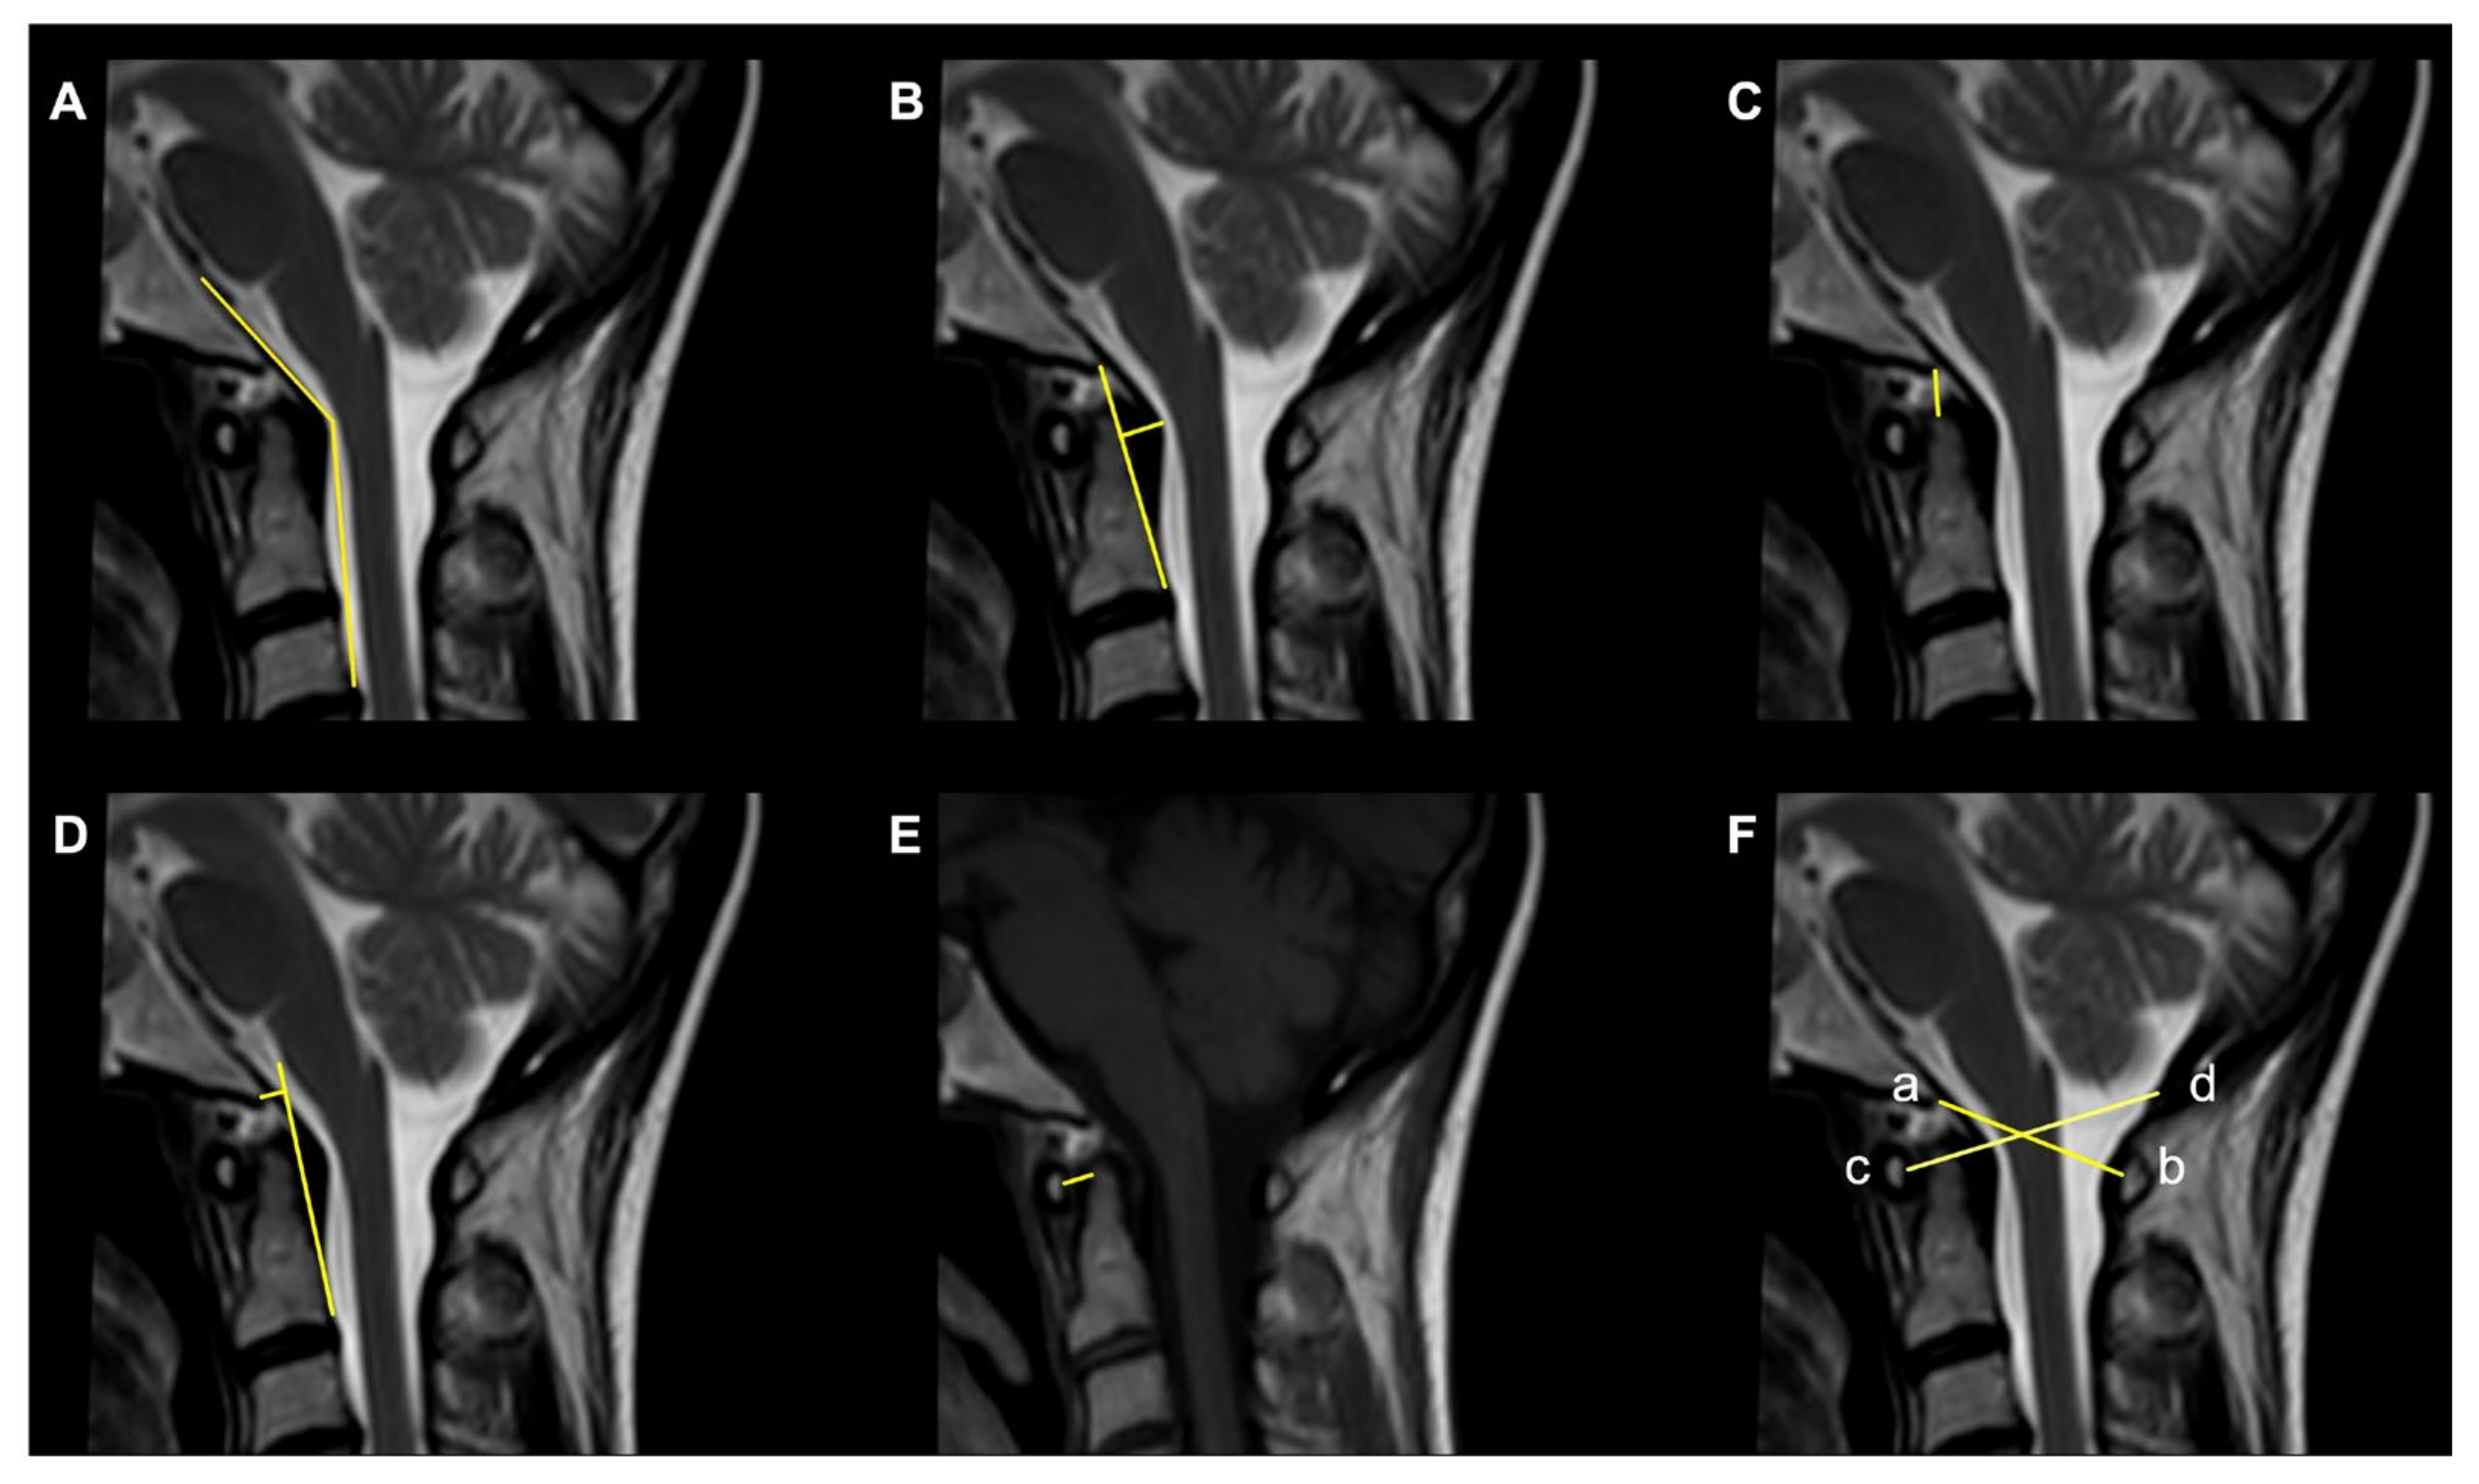

Figure 3.

Commonly used radiological parameters to predict CVJ instability. (A) Clivoaxial Angle (CXA). (B) Grabb–Oakes line. (C) Basion–Dens Interval (BDI). (D) Basion–Axial Interval (BAI). (E) Atlantodental Interval (ADI). (F) Powers ratio: ab/cd.

- The Clivoaxial Angle (CXA), which is the angle between the clivus line and the posterior axial line, examines the brainstem deformity induced by the odontoid process. A CXA of 135 degrees or less is considered “potentially pathological” [71].

- The Grabb–Oakes line, which is the perpendicular distance from the dura to the line drawn from the basion to the posterior inferior edge of the C2 vertebra. It is a measure of the encroachment of the odontoid process into the upper spinal canal (basilar invagination) and investigates ventral brainstem compression. A measurement ≥9 mm is considered pathological [68].

- The Basion–Dens Interval (BDI) measures the vertical distance between the basion and the dens and is considered pathological if ≥10 mm [72].

- The Basion–Axial Interval (BAI) is the distance from the tip of the basion to the posterior axial line and is pathological if ≥12 mm [72].

- The translational BAI and translational BDI are the change in mm of the BAI and BDI between the flexion and extension positions of the head [68].

- The Atlantodental Interval (ADI) is the distance between the posterior surface of the anterior atlas ring and the anterior surface of the odontoid process. An ADI >5 mm in adults and >4 mm in children is an indication for surgery [73].

- The Condyle–C1 interval (CC1) measures the distance between the occipital condyle and C1 at four equidistant points and is pathological in children if >4 mm, with a high diagnostic accuracy [73].

- The Powers ratio is calculated by measuring the distance between the basion and the posterior arch of the atlas and then dividing it by the distance between the opisthion and the anterior arch of the atlas [74].